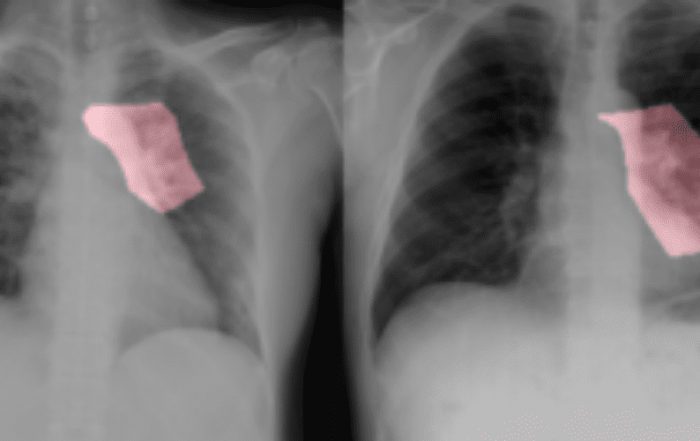

Confidence Calibration for a more reliable AI

A team of computer scientists at the Lawrence Livermore National Laboratory (LLNL), a federal research facility founded by the University of California, Berkeley proposed the use of Confidence Calibration for a more reliable classifier model to predict disease types based on diagnostic images. In a